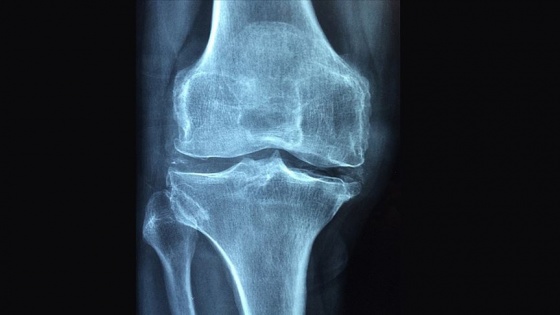

Romatizmal hastalıkların aynı zamanda osteoporoz gelişimi için de bir risk faktörü olduğunu vurgulayan Günendi, "Yapılan çalışmalarda iltihabi romatizmal hastalığı olanlarda, aynı yaş ve cinsiyetteki sağlıklı kişilere göre osteoporoz görülme sıklığının arttığı gösterilmiştir." dedi.

Bağışıklık sisteminde, hücreler arası etkileşimi sağlayan sitokin adı verilen protein yapıların olduğunu anlatan Günendi, "Bunların bazıları iltihabı tetiklerken bazıları da iltihap gelişimini önlemektedir. Sağlıklı kişilerde sitokinler denge içinde bulunurken, romatizmal hastalığı olan bireylerde sitokin dengesi, iltihabı tetikleyen sitokinlere doğru kaymaktadır. Romatizmal hastalıklarda artmış iltihap tetikleyici sitokinler, aynı zamanda kemik yıkımını da hızlandırmaktadır." diye konuştu.